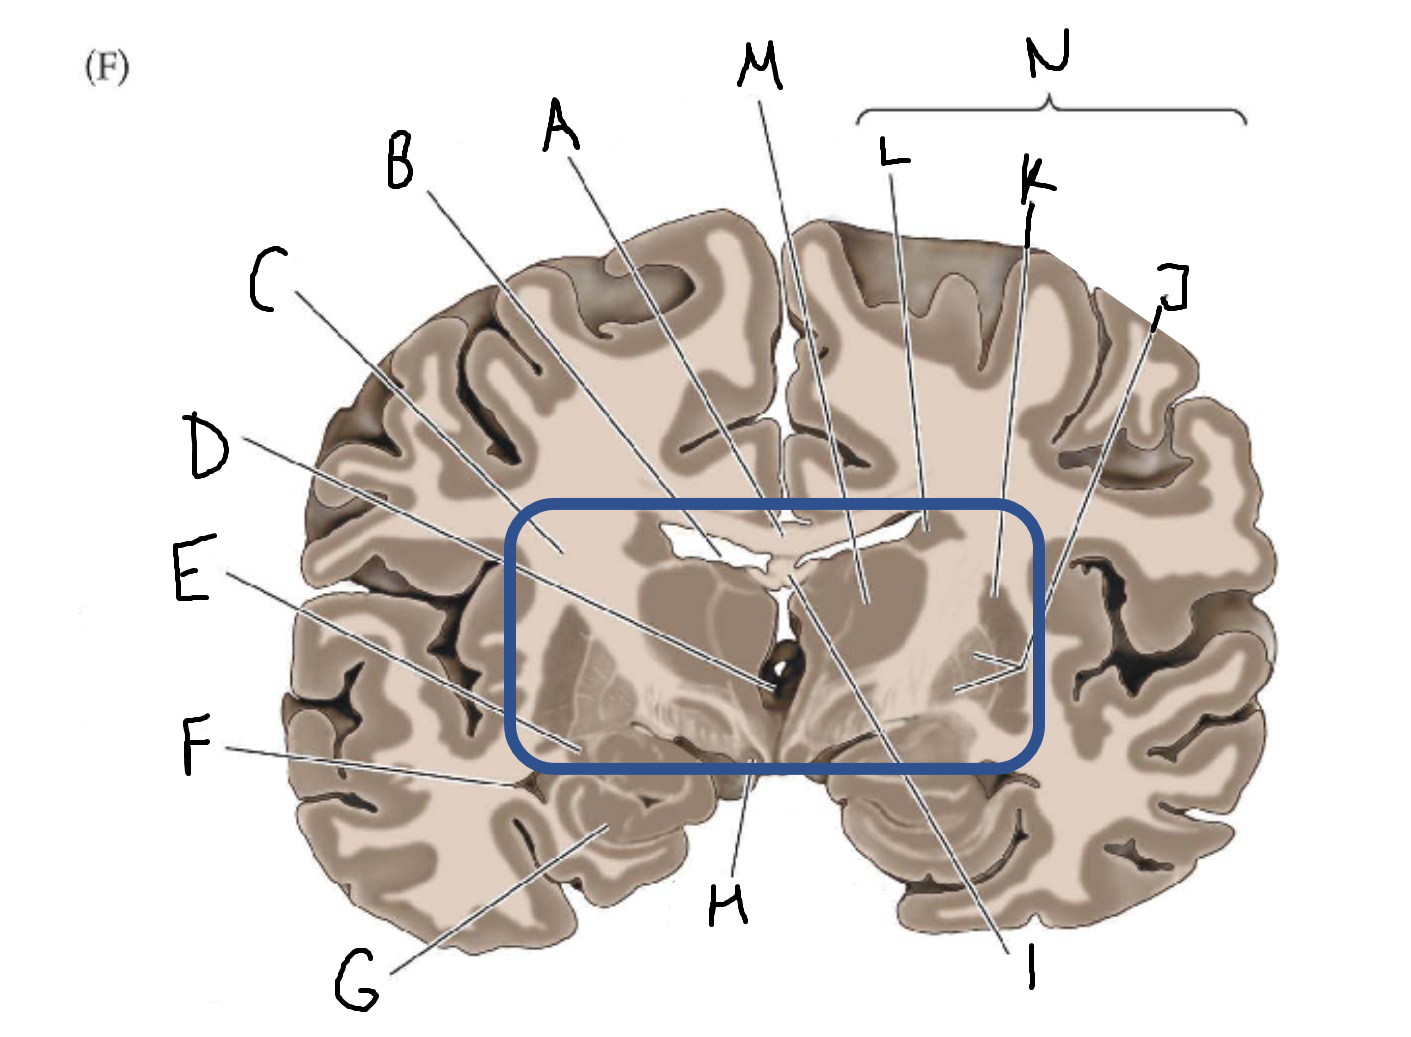

A

corpus callosum

B

lateral ventricle

C

internal capsule

D

third ventricle

E

tail of caudate nucleus

F

lateral ventricle

G

hippocampus

H

mammillary body

I

fornix

J

globus pallidus

K

putamen

L

caudate

M

thalamus

N

basal ganglia